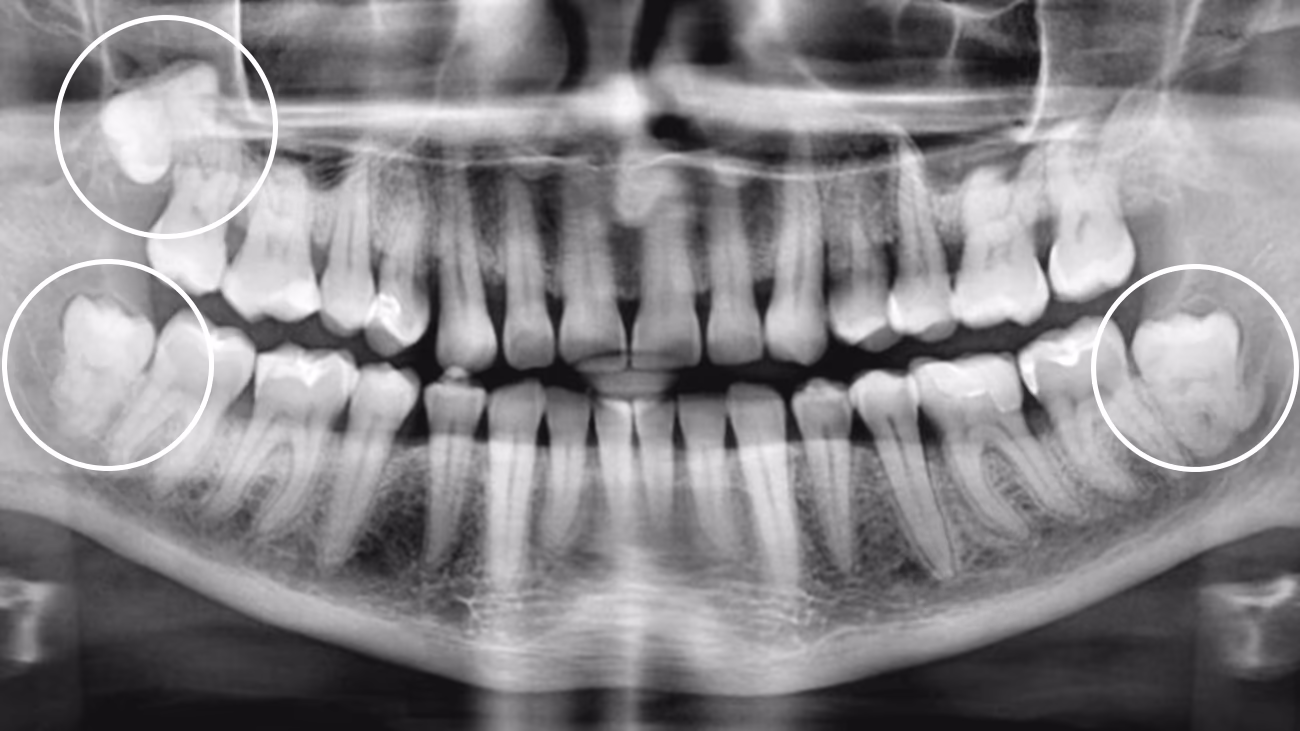

Так, у багатьох випадках видалення рекомендують навіть за відсутності болю. Ризики можуть виникати без симптомів:

• зуб росте під кутом або частково залишається в яснах

• він тисне на сусідній зуб і може зміщувати прикус

• у ділянці зуба накопичується їжа, що викликає запалення ясен і карієс

Так. КТ є обов’язковою для точного та безпечного видалення зуба мудрості.

3D-діагностика дозволяє визначити:

• положення зуба

• напрямок росту

• особливості коренів

• близькість до нижньощелепного нерва або верхньощелепної пазухи

У Sergatiy Dental Clinic КТ є обов’язковою перед видаленням зуба мудрості. Без КТ значно підвищуються ризики ускладнень.